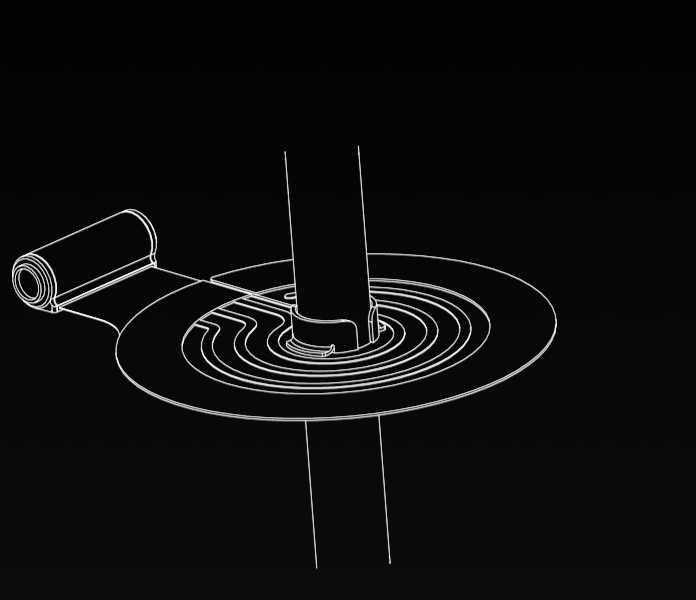

Dual Lumen Cannula

16 Novel Claims

The proprietary Convertible Dual Lumen Cannula is uniquely designed to offer multiple uses with intravascularly converting from a single-lumen cannula into a dual-lumen cannula after initial insertion. The unique cannula may potentially allow for fast action and reduced risk, complications and additional infection points.

An essential tool in a wide range of medical settings

A dual-lumen cannula is often used for the simultaneous venous drainage and reinfusion of blood during processes such Extra-Corporeal Membrane Oxygenation (ECMO) in Intensive Care Units (ICUs).

An essential tool in a wide range of medical settings

A dual-lumen cannula is often used for the simultaneous venous drainage and reinfusion of blood during processes such Extra-Corporeal Membrane Oxygenation (ECMO) in Intensive Care Units (ICUs).

Dual lumen cannula

- Granted in the U.S., 2023*

- Granted in the U.S., 2023

- Filed in Europe, China, Korea, Japan, Israel

A cannula fixation device

- Granted in the U.S. 2024

- Granted in Israel, 2022